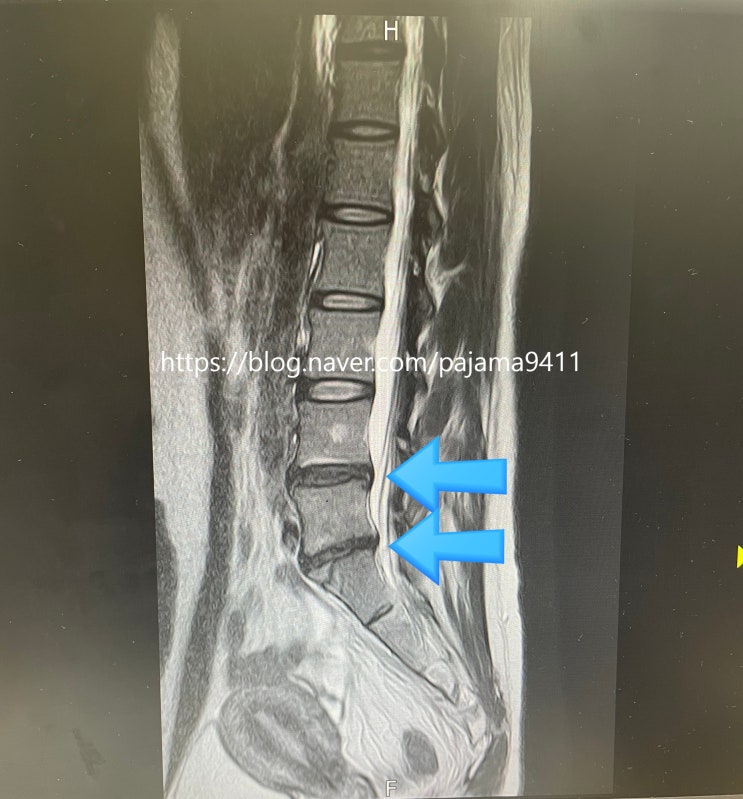

[허리디스크 통증] 도수치료,신경주사,백년허리 허리 숙이지 말라

6월부터 몇 달째 허리 통증 중인 김션입니다. 오죽했으면 제가 그날그날 허리 상태를 이렇게 메모했을까요?...

허리디스크 환자의 요즘 (정성근교수님,백년허리, 걷기운동)

깡총이가 두살때쯤인가 깡총이는 대근육발달이 많이 늦은편이라 늦게 걸었다. 그래서 무거운 아이를 아기띠...

허리디스크 환자 필독서 :: 백년허리 (정선근)

허리디스크 진단을 받고 유튜브 영상을 찾아보다가 서울대학교 '정선근교수'에 대해 알게 되었다...